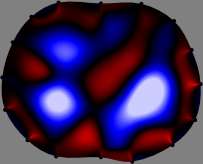

Figs. 3 and 4 compare the performance of the proposed FER method in (20) with the standard regularized least-squares method ((19) when \mathcal{R} is the identity matrix). The regularization parameter of the standard method was heuristically chosen for its best performance, and the parameter of the FER method was set to be one of three different values λ=0.05,0.2,𝜆0.050.2\lambda=0.05,0.2,\infty. The injection current was 1 mARMSRMS{}_{\tiny{\mbox{RMS}}} at 100 kHz, and the frame rate was 9 frames per second. The reference frame at t0subscript𝑡0t_{0} was obtained from the maximum expiration state. The measured data, 𝐕˙(tm)˙𝐕subscript𝑡𝑚\dot{\mathbf{V}}(t_{m}), represent the voltage differences between each time tmsubscript𝑡𝑚t_{m} and t0subscript𝑡0t_{0}. The blue regions, which denote where conductivity decreased by inhaled air, increased during inspiration and decreased during expiration. The FER method with λ=𝜆\lambda=\infty was clearly more robust than the standard method that produced more artifacts originated from the inversion process.

Figure 4: The reconstructed images of the conductivity change of the subject B by the standard regularized least square method and the proposed fidelity-embedded regularization (FER) method for three difference values λ=0.05,0.2,𝜆0.050.2\lambda=0.05,0.2,\infty. Here, the time step is 0.55 seconds (tm+5tm0.55subscript𝑡𝑚5subscript𝑡𝑚0.55t_{m+5}-t_{m}\approx 0.55).